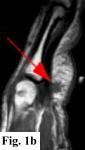

MRI FINDINGS:   MRI was performed on AIC's high-field 1.5 Tesla short-bore Siemens Symphony scanner using a small flexible surface coil. Fig. 1a is a high-resolution coronal DESS, Fig. 1b a sagittal T1 weighted, Fig. 1c a sagittal turbo STIR, and Fig. 1d an axial T1 weighted. They demonstrate a 5x5x7 mm nodule in the volar aspect of the hand at the level of the 4th MCP joint inseparable from the flexor digitorum superficialis tendon (arrows) with some adjacent soft tissue edema. The underlying tendon and bones are otherwise intact.

SURGICAL-PATHOLOGIC DIAGNOSIS:   The patient was taken to surgery at LCH by Dr. Rahmati and a "rather solid round mass attached to the volar aspect of the 4th tendon sheath" (arrows in Fig. 2a-b) was excised measuring about 4x4x3 mm. Pathology at LCH revealed a "grayish-white somewhat nodular smooth soft tissue measuring 9x8x5 mm" with histopathologic "features in favor of a giant cell tumor of tendon sheath" interpreted as benign.